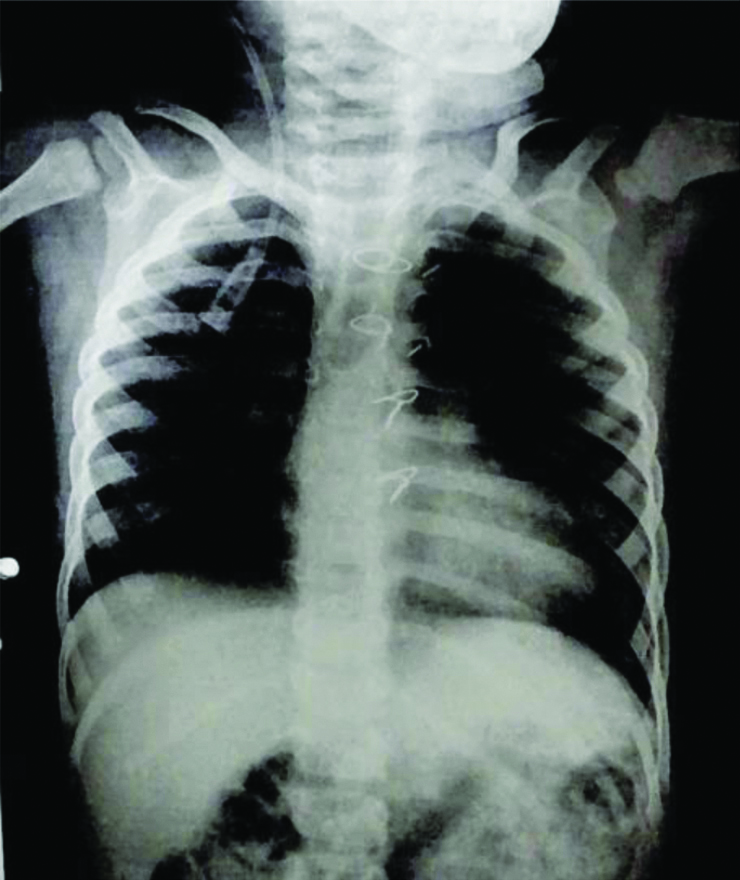

The chest X-ray revealed normal bilateral lung fields and a boot-shaped heart [Table/Fig-2]. The ECG showed no abnormalities and the 2D echocardiogram confirmed the post-VSD closure status, with the VSD patch intact, no signs of Pulmonary Artery Hypertension (PAH) and a Left Ventricular Ejection Fraction (LVEF) of 67%. Laboratory results included a haemoglobin level of 11.7 g/dL, White Blood Cell (WBC) count of 8700/μL, platelet count of 140,000/μL, Prothrombin Time (PT)/International Normalised Ratio (INR) at 12.6/1.1 seconds, urea at 31 mg/dL and creatinine at 0.37 mg/dL. Both liver function tests and serum electrolytes were within normal limits. Written and informed consent was obtained from the parents after a clear explanation of the anaesthesia procedure and the associated risks, including the potential challenges related to a difficult airway. The patient was classified as ASA grade 2 under the American Society of Anaesthesiologists.